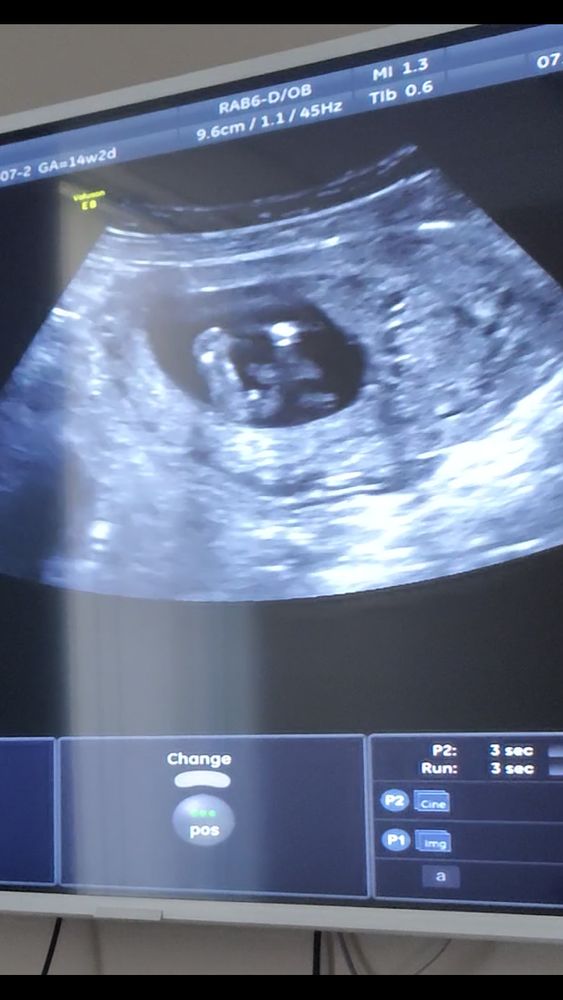

Мальчик или девочка? Фото узи

Здесь более вероятен женский пол. А торчит - половой бугорок. В данном случае - клитор))

А почему все за девочку? 😄на первой фотографии похожа, а на остальных же прям торчит что-то, что не очень на девочку похоже))